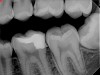

Fig 15. Preoperative radiograph. Courtesy of Dr. Sam Kratchman.

Figure 15

Fig 16. Post apicoectomy. Courtesy of Dr. Sam Kratchman.

Figure 16

Fig 17. Retropreps and isthus filled. Courtesy of Dr. Sam Kratchman.

Figure 17

Fig 18. 20-month follow-up with BC putty shows complete healing. Courtesy of Dr. Sam Kratchman.

Figure 18